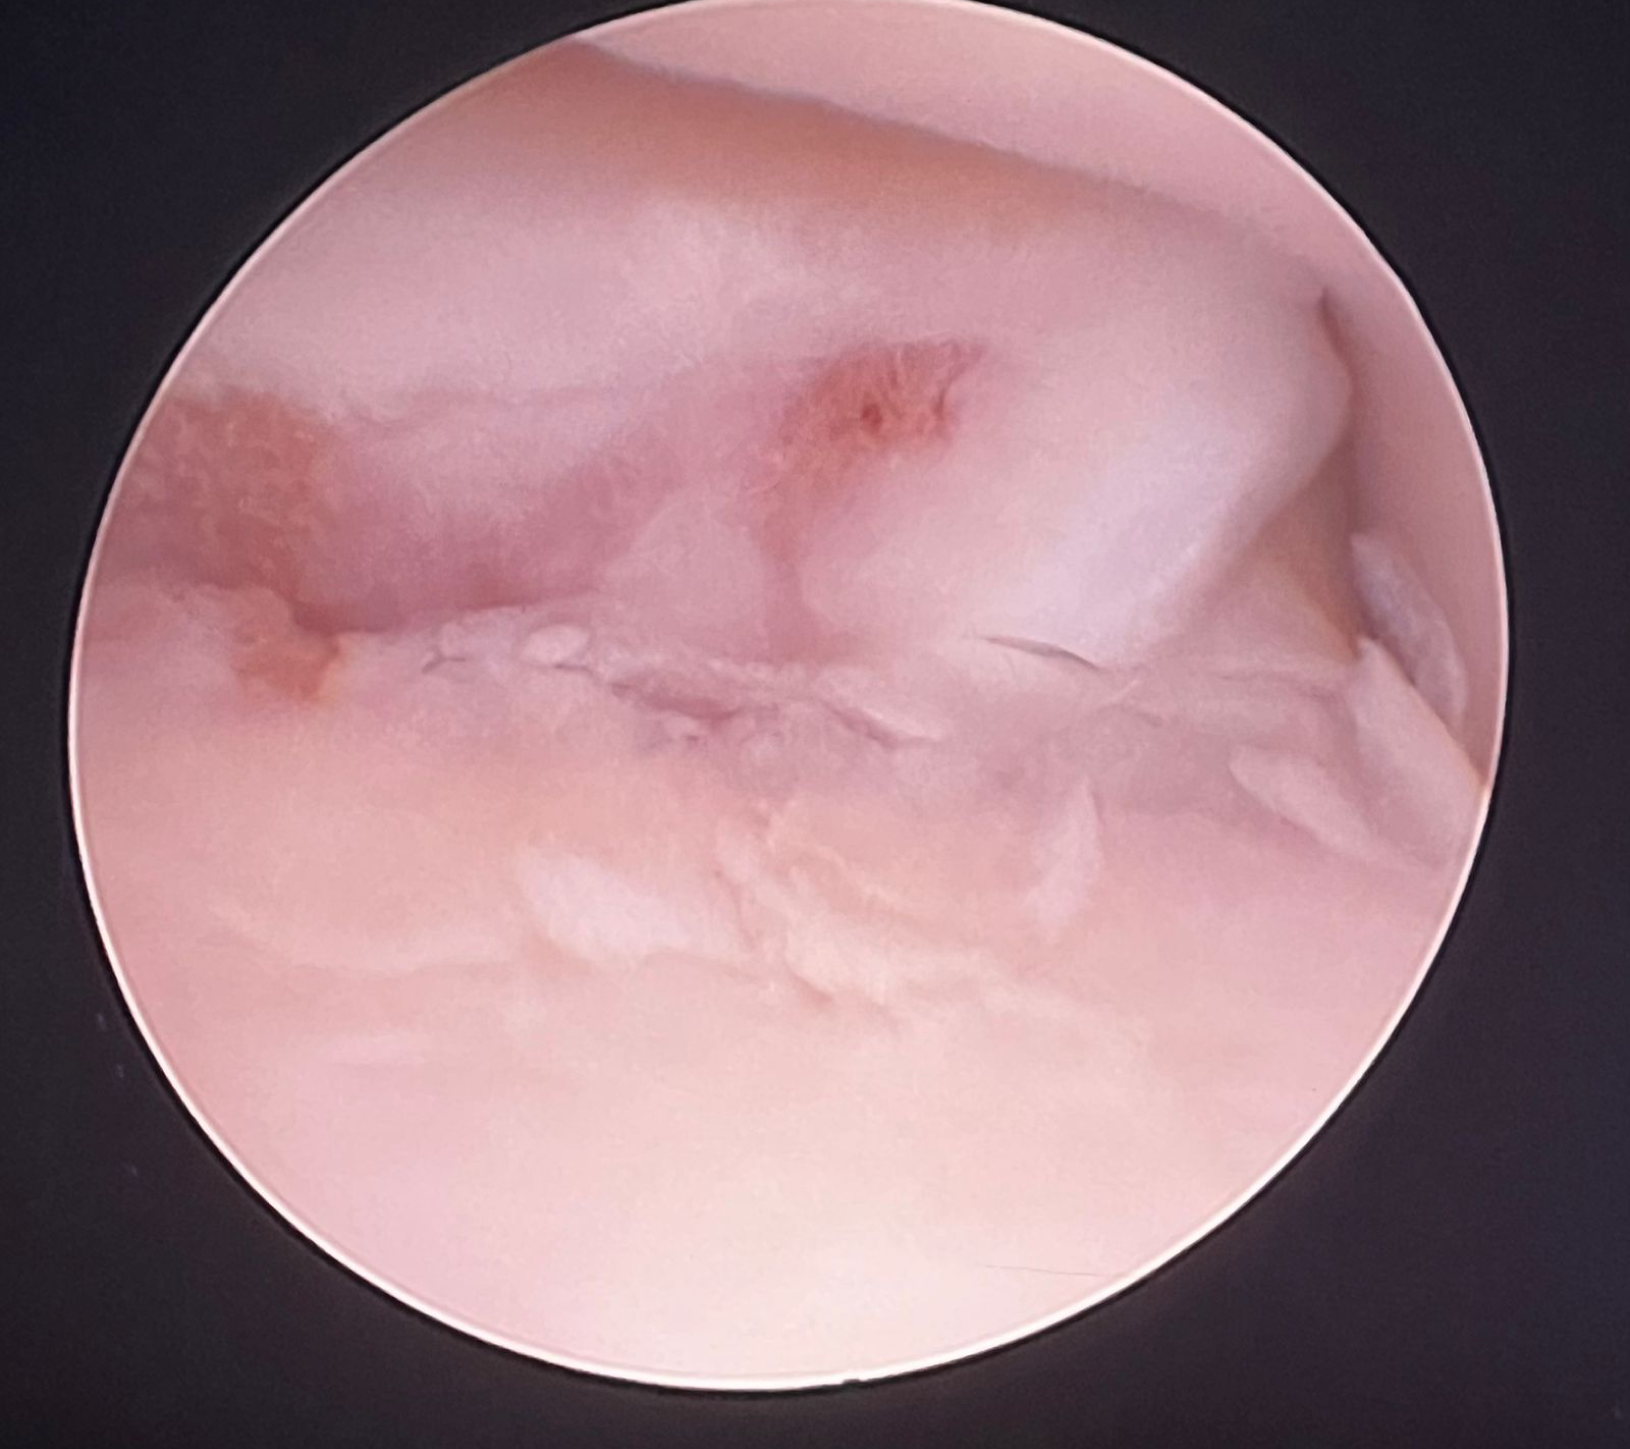

La artroscopia (introduciendo una pequeña cámara dentro de la articulación) supone un apoyo diagnóstico al TAC, ya que permite visualizar el cartílago articular (cosa que no hace el anterior). Al mismo tiempo permite tratar la mayoría de lesiones asociadas a la patología (retirar fragmentos, etc.)

• RETIRADA DEL FRAGMENTO: La retirada de los fragmentos libres de cartílago y hueso puede reducir las molestias articulares. Ésto se puede llevar a cabo bien utilizando un artroscopio (técnica artroscópica) o mediante artrotomía (abordaje quirúrgico convencional a la articulación mediante una incisión). Actualmente es más habitual emplear el primer método pues se trata de una técnica de mínima invasión, donde entre otras ventajas, se consigue una recuperación más rápida en la mayoría de casos. Desafortunadamente la cojera puede llegar a no mejorar en algunos pacientes, siendo atribuible en muchas ocasiones a la presencia de incongruencia articular y / o una osteoartritis avanzada.

• Enfermedad del proceso coronoides medial (EPCM): se trata de la condición más encontrada de todas las que se incluyen en la displasia de codo. El proceso coronoides puede encontrarse malformado, fisurado e incluso fragmentado. Como resultado de esta enfermedad y del roce anormal de dicha estructura con la superficie articular del cóndilo humeral medial, se produce un desgaste acelerado de las superficies cartilaginosas del aspecto medial del codo dando lugar al Síndrome del compartimento medial, el cual se ve favorecido por la sobrecarga que soporta la región interna de la articulación en condiciones fisiológicas.